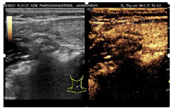

入院后行甲状腺超声示甲状腺左叶上、下极深方甲状旁腺区见2个囊实性结节,大小分别为2.9cm×1.4cm×1.1cm、2.3cm×1.4cm×1.2cm,均形态规则,边界清晰,CDFI:内见较丰富血流信号(图1,图2,图3,图4)。行甲状旁腺融合显像(显像剂:99Tcm-MIBI)示甲状腺左叶上极后上方见结节样显像剂浓聚灶,相应CT层面示椭圆形软组织密度影,边界清,大小约27.6mm×18.2mm×16.0mm。CT另见甲状腺左叶下极后下方一椭圆形软组织密度影,边界较清,大小约25mm×13.7mm×12.5mm,相应ECT层面未见显像剂摄取(图5,图6)。行嗜铬细胞瘤融合成像(显像剂:131I-MIBG)示颈部及腹部可见显像剂摄取病灶(图7,图8)。

超声图像中左侧甲状旁腺区2枚囊实性结节形态、回声、位置及血流均相似,结合实验室检查及临床病史,均提示为甲状旁腺腺瘤,但甲状旁腺融合成像仅支持甲状腺左叶上极后方结节为甲状旁腺腺瘤。甲状腺左叶下极后方结节无99Tcm-MIBI显像剂摄取,但有131I-MIBG高摄取,故综合以上考虑甲状腺左叶上极后方结节为甲状旁腺腺瘤,左叶下极后方结节为副神经节瘤。